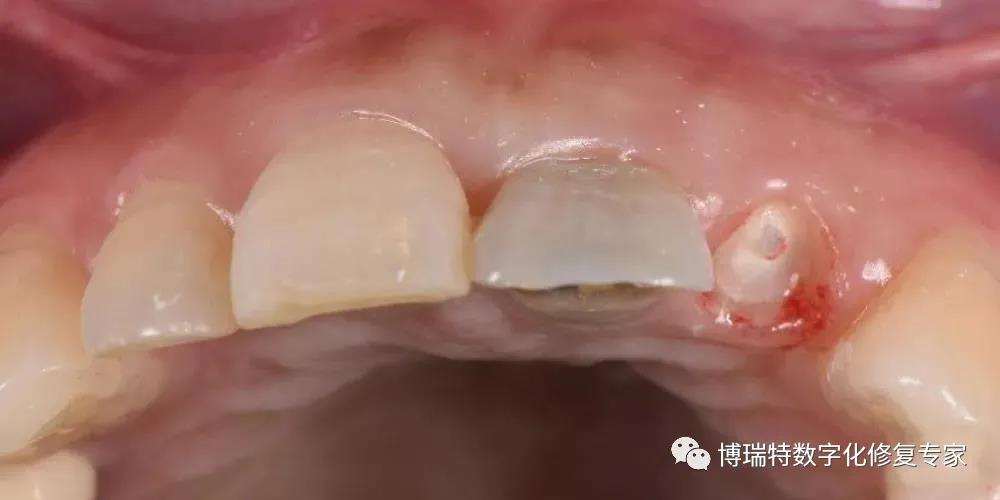

8226; 局麻下,微创拔除21患牙,图见 21 牙冠与牙根完全分离;

8226; 仔细探查唇侧骨壁,骨壁完整,偏腭侧制备种植窝洞,植入Straumann Roxolid® SLActive® BLT 3.3mm×14mm 种植体;

8226; 种植体三维位置良好,位于理想龈缘根方3mm-4mm;

8226; 种植体植入扭矩大于35N.cm;

8226; 种植体与唇侧骨板2mm以上的跳跃间隙,间隙内植入骨粉;

8226; 安装愈合基台;

8226; 术后CBCT 。